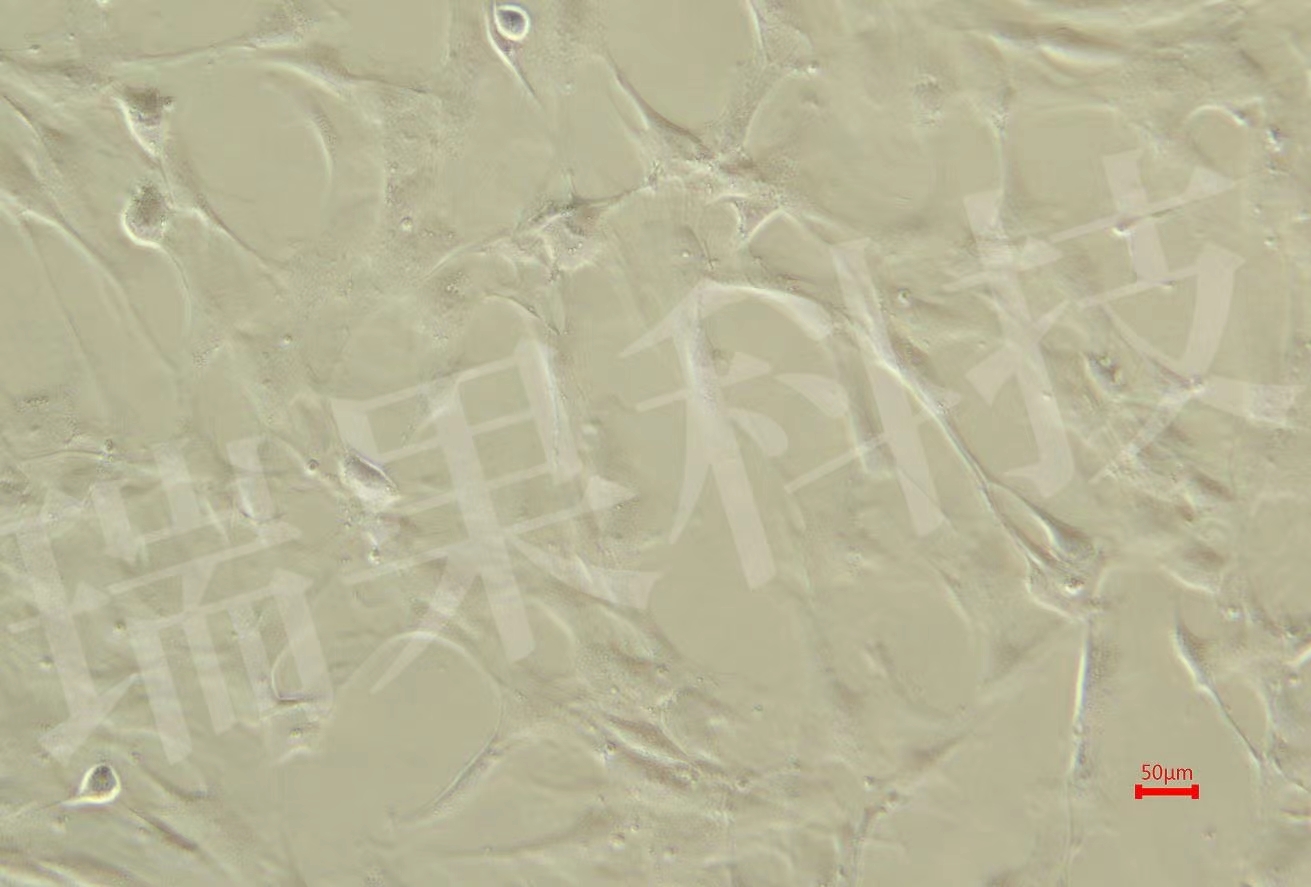

过碘酸-雪夫(Pexiodic acid-schiff,PAS)染色又称糖原染色。胞浆内存在的糖原或多糖类物质(如黏多糖、黏蛋白、糖蛋白、糖酯等)中的乙二醇基(CHOH-CHOH)经过碘酸(Periodic acid)氧化,转变为二醛基(CHO-CHO),与雪夫(Schiff